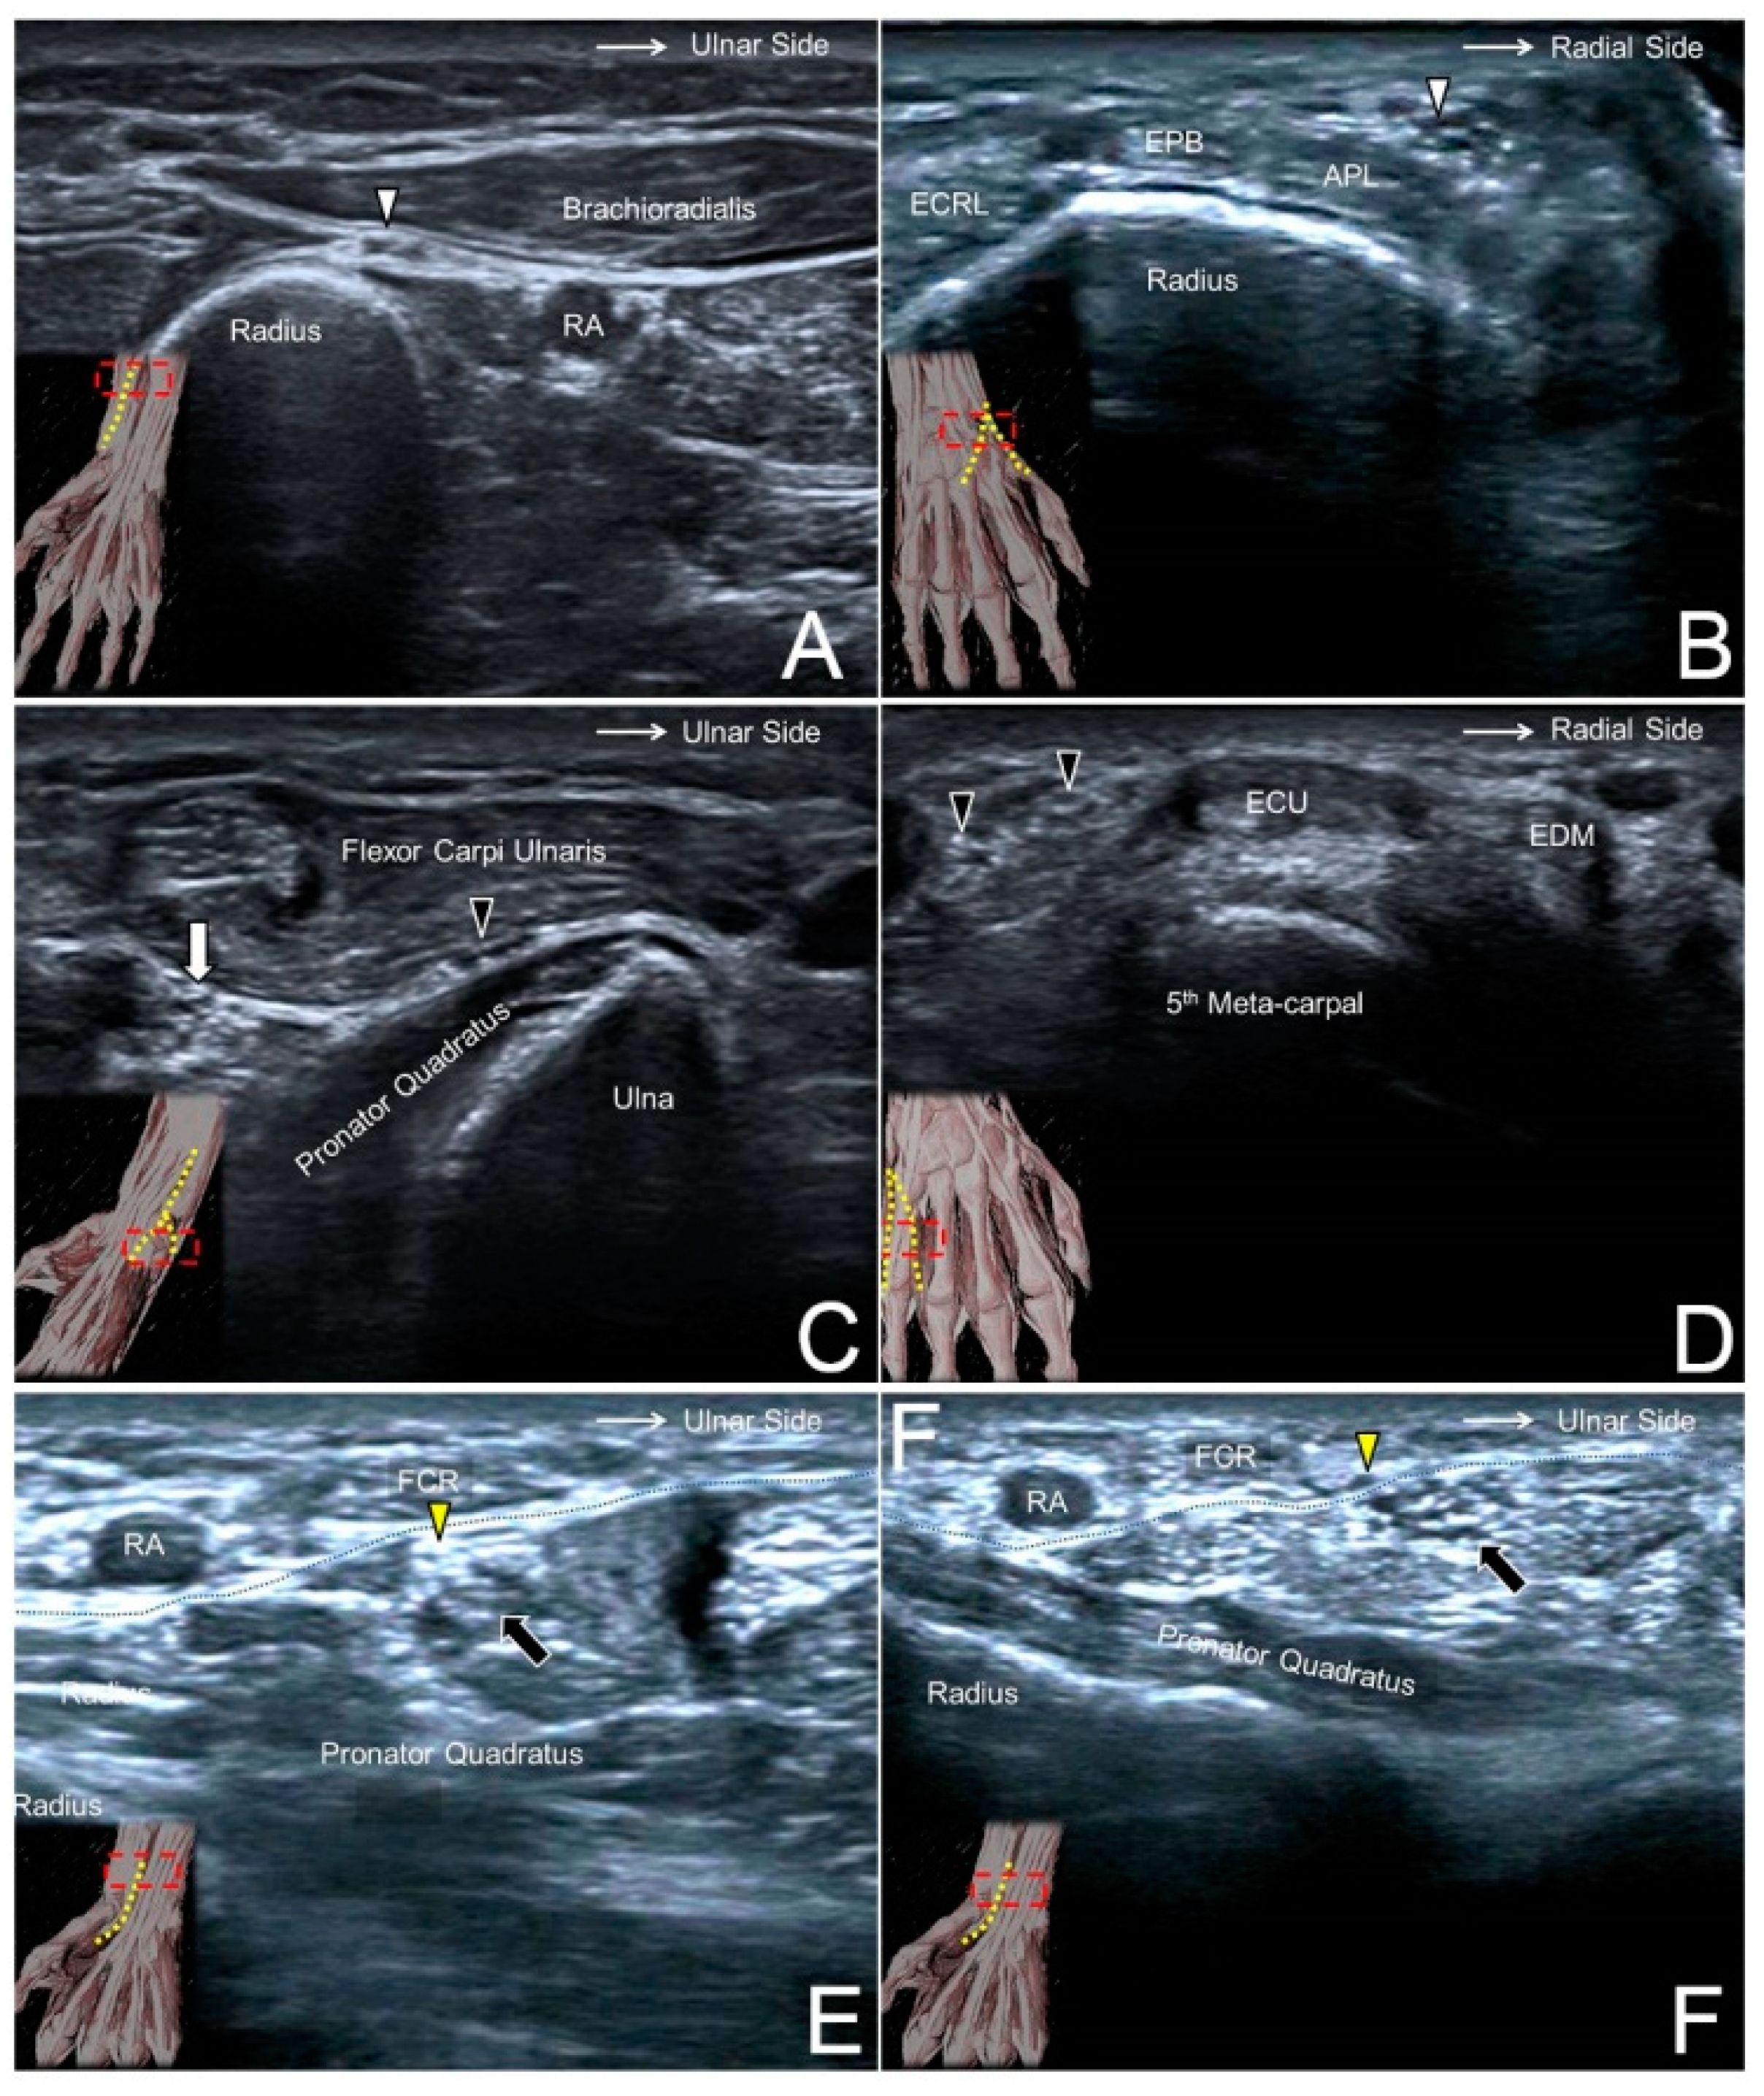

Ultrasoundguided Local Anaesthetic Blocks Of The Forearm Virtual Library

Ultrasoundguided Local Anaesthetic Blocks Of The Forearm Virtual Library Ulnar Nerve Block Ultrasound 7 additionally, analgesia can be achieved without local infiltration which distorts the wound, thereby enabling easier skin closure and a more aesthetically pleasing result. The median nerve is commonly found anteromedial to the artery, the ulnar nerve medial to the artery, and the radial nerve posteromedial to it, along the conjoint tendon (fig. The musculocutaneous nerve often branches off more. Ulnar Nerve Block Ultrasound.